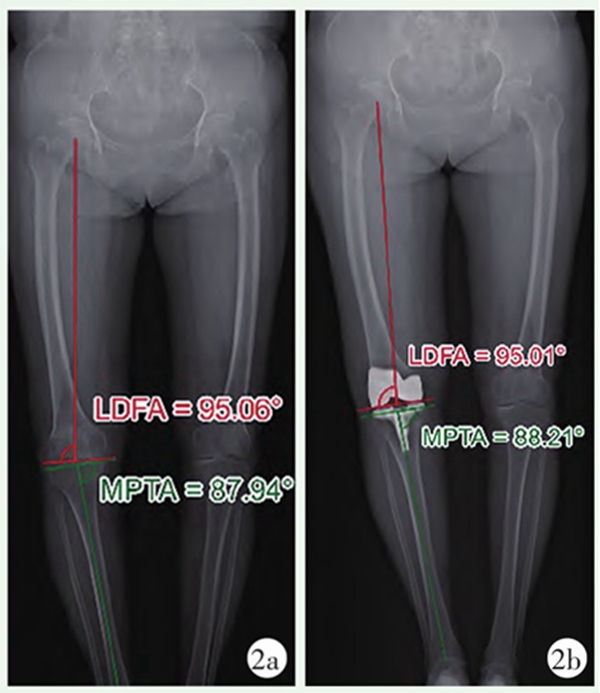

图2 KA-TKA患者双下肢站立位全长X线片

2a:术前X线片;2b:术后X线片患者术前股骨及胫骨排列予以完全保留;LDFA:股骨远端外侧角;MPTA:胫骨近端内侧角